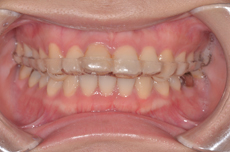

- 口を開けると顎がカクカク、ジャリジャリなどの音がする

- 口が開け難い、開かない

- 顎が痛い

などの症状は関節内の組織に何らかの異常があることが考えられます。それに対して通常のレントゲン写真では骨しか写りませんので、それ以外の組織の異常までは診断できません。当院ではMRIを撮って診断した後、顎関節専門医の院長が治療にあたります。